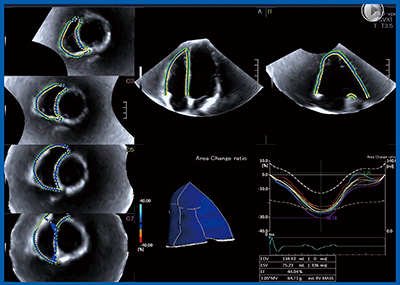

東芝メディカルシステムズ社の右室専用のストレイン解析ソフトウエアは,筑波大学との共同研究により開発されたもので,ヒツジによる実験では,3D Speckle Trackingでのストレイン値と超音波クリスタル法で算出されたストレイン値は非常に良く相関し,特にACRは最も良い相関が得られ,右室の3D評価として非常に有用性が高いことが報告されている4)。そこで,当院にて臨床で応用し,右室の流入路,心尖部,流出路がすべて網羅されている3D-RV WMT によるACRを用いてPAH症例の右室機能評価を行い,詳細な右室機能評価が可能であった(図5)。さらに,本ソフトウエアでは右室が7分画に分けられているが,心筋全体の評価に加えて各分画のストレインカーブの描出が可能であった(図6)。ArtidaによるPAH 109症例の3年間の長期予後評価を行ったところ,従来法(2D)での右室機能評価よりも,3D Speckle TrackingによるACRが最も有用な予後評価因子であった。

図5 右室専用のストレイン解析ソフトウエアによる

3D-WMT解析結果

図6 右室の7分画のストレインの計測